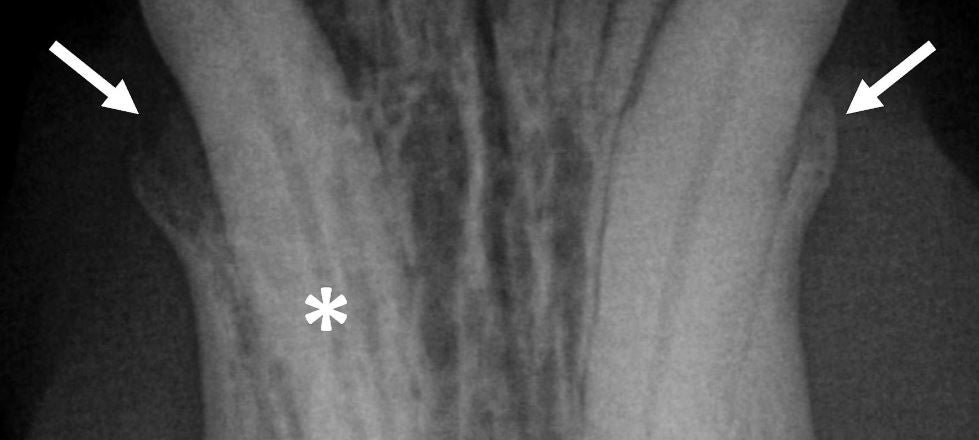

dental radiograph

This webinar will review equipment/material needs to perform dental radiography in dogs and cats. Benefits and disadvantages of digital and non-digital options are outlined. Parallel and bisecting angle techniques and the most common positioning mistakes are discussed. Anatomy and pathology on numerous dental radiographs obtained from the upper and lower jaws with various lesions are explained in a systematic fashion. The didactic lecture will last 1.5 hours, but the webinar is designed so that there is extra time for interactive participation and answering your questions.